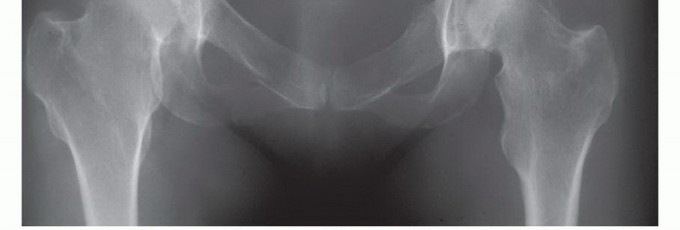

- الأشعة السينية (X-rays): هي الفحص الأولي، ويمكن أن تكشف عن التغيرات العظمية مثل التآكل أو التصلب أو الكسور.

- التصوير المقطعي المحوسب (CT Scan): يوفر صورًا مقطعية مفصلة للعظام والأنسجة الرخوة، ويساعد في تحديد حجم الورم، مدى انتشاره داخل العظم، وعلاقته بالهياكل المحيطة.

- التصوير بالرنين المغناطيسي (MRI): يُعد الأداة الأكثر حساسية لتقييم الأنسجة الرخوة ونخاع العظم، ويكشف عن النقائل في مراحلها المبكرة، ويحدد مدى انتشار الورم في القناة الشوكية أو الأعصاب.